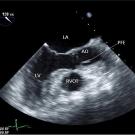

Hinduja Nallamala, DO; Lannie Cation, MD

A 66-year-old man presented to the hospital with hypoxia requiring 15 L/min of supplemental oxygen. The patient’s medical history included non-ischemic cardiomyopathy with systolic heart failure, a left...